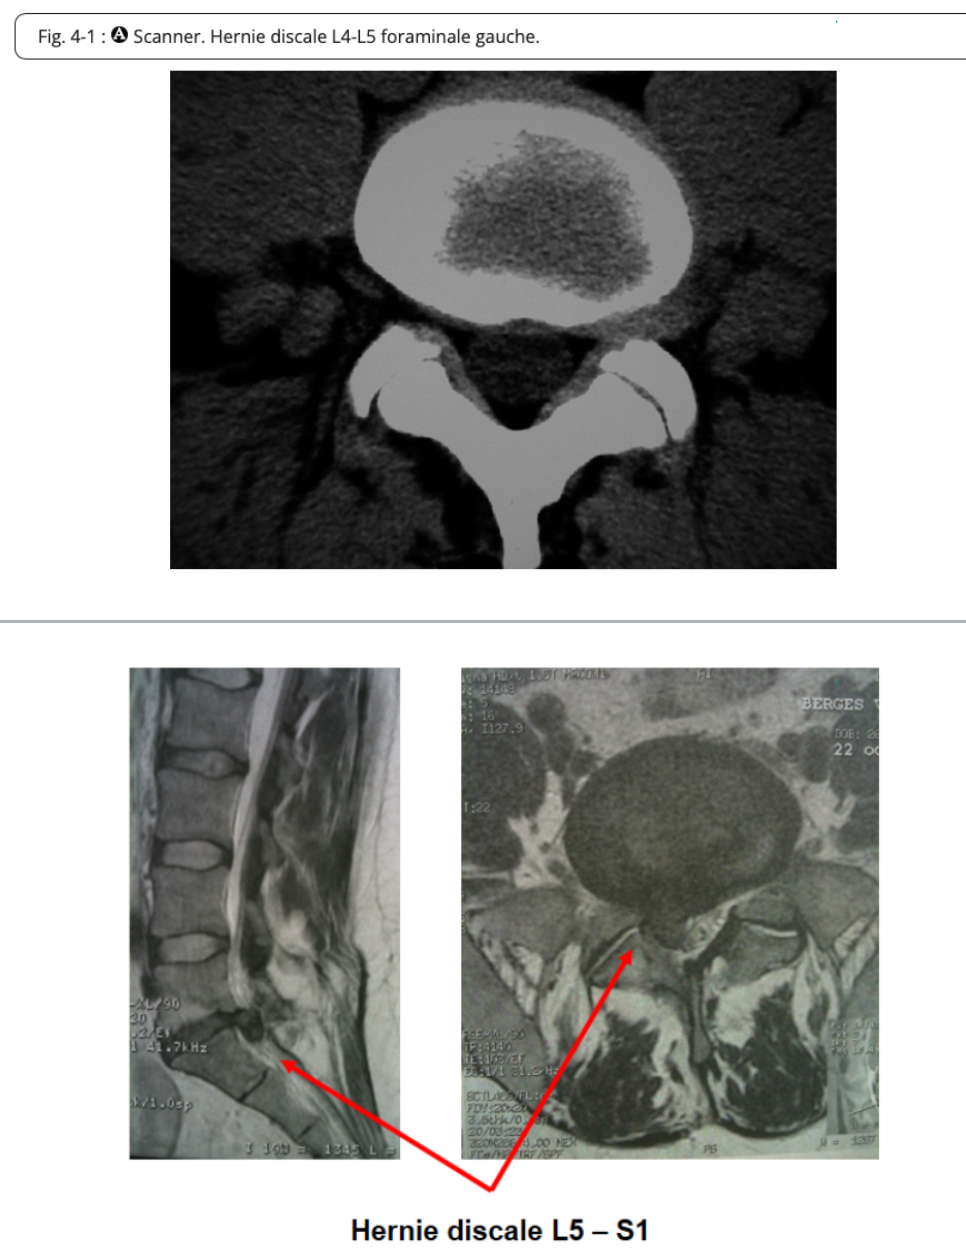

Hernie discale

=lésion atteignant le rachis et caractérisée par le déplacement d’une partie d’une disque intervertébral hors des limites de sa position initiale → ouverture de l’anneau fibreux laissant passer une partie du noyau pulpeux